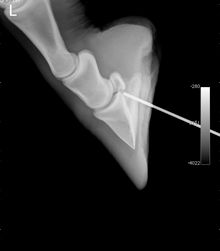

Lavage of a horse's hoof after the patient stepped on a nail.Aside from the breeding population and racing component of Saratoga Springs there is a large population of pleasure horses that benefit from a centrally located referral hospital. “Late one afternoon recently a family was bringing their 20-year-old retired pleasure horse in from his pasture and noticed he was limping,” notes Tull. “Further inspection demonstrated a hole in his hoof in the region of the frog, and a nail in a board nearby with blood on it. They got him on the trailer and brought him in to the hospital. The wound was cleaned a radiograph taken with a sterile probe in place. The nail had penetrated through the frog and entered the navicular bursa and the distal interphalangeal joint, important synovial structures within the hoof. The horse was taken to surgery that night, the nail tract cleaned and debrided, and the navicular bursa and distal interphalangeal joint flushed copiously with sterile fluid.”

Hoof radiograph showing a sterile probe into the wound.A regional limb perfusion, a procedure where a tourniquet is placed above the hoof and antibiotics placed within a vessel resulting in a high antibiotic concentration in the region, was also performed during the procedure. “The goal when a synovial structure is penetrated is to remove contaminants and bacteria to prevent a life-threatening infection from occurring,” Tull says. “The sooner wounds like this are treated appropriately, the more likely the horse will avoid infection and chronic lameness. This patient received intravenous antibiotics, further regional limb perfusions performed standing, and a special shoe with a treatment plate custom-made by the practice podiatrist. He made a full recovery and is sound and living the good life of retirement.”